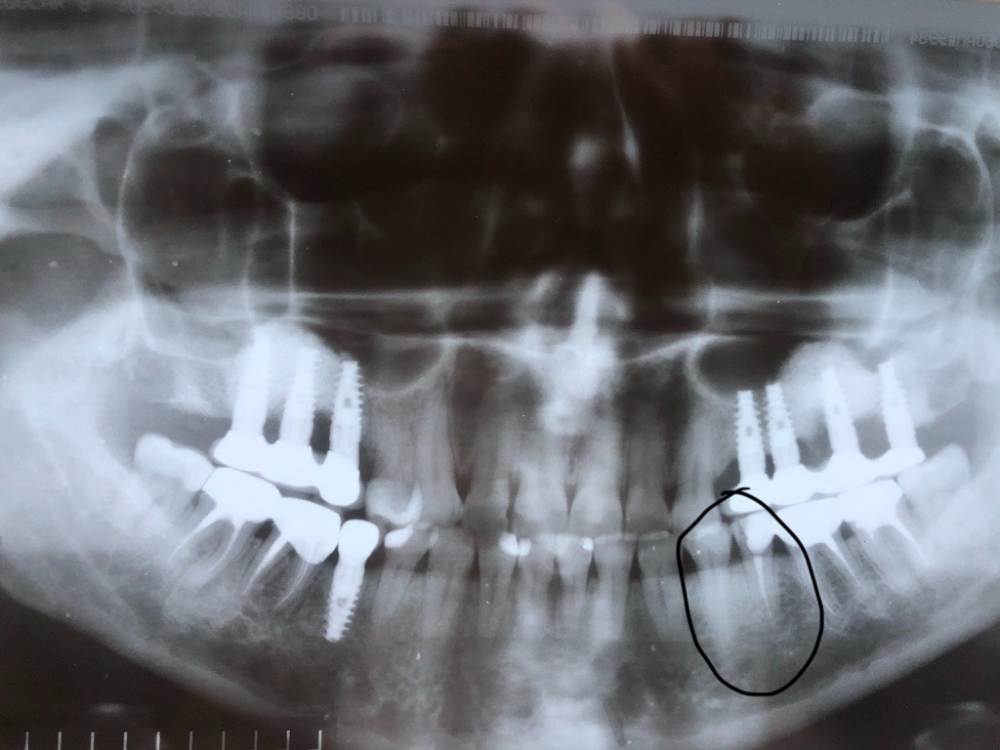

Панорама до удаления и установки импланта. Прицельные сделали вчера до депульпирования 34.

И еще вопрос по модели импланта, мне сказали, что немецкий. Можно как-то определить по снимку?

Зуб 3.5, а не 4.6, понять по снимку немецкий или нет сложно (желательно знать конкретную марку), по снимкам ничего криминального нет, но если причина болей в импланте то снимки ещё недели две ничего и не покажут.

Спасибо за быстрый ответ! Исправила в теме номера зубов. А что-нибудь можете сказать про 34 зуб по снимкам? Есть ли там пародонтоз, как мне сказали, и что это из-за него возникли боли. Что когда установили имлантат, то организм включил иммунные процессы и в этом зубе активизировались боли из-за пародонтита( которого никогда не ощущала раньше)